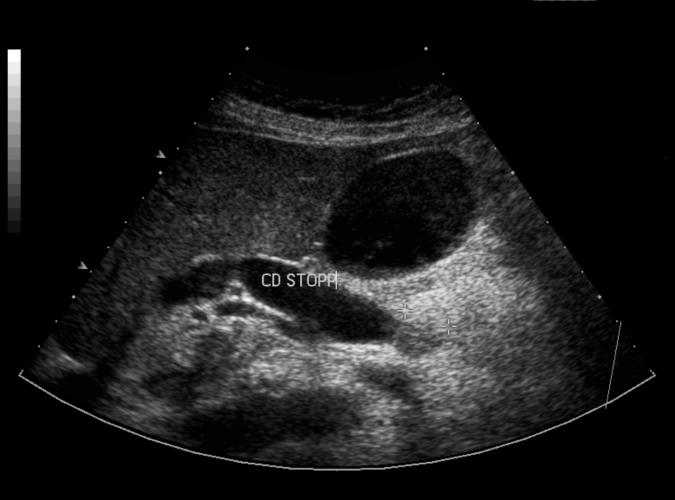

Samma patient som i bild 7a. Long bild av tumören i caput pancreas som stryper ductus choledochus. Whipple.op adenocarcinom